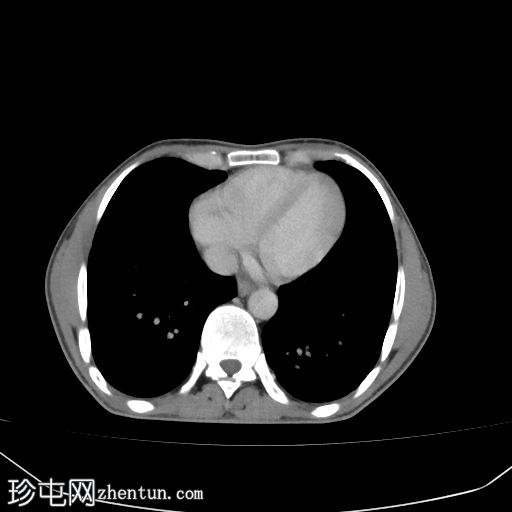

腹部(肝脏)CT

轴位

平扫